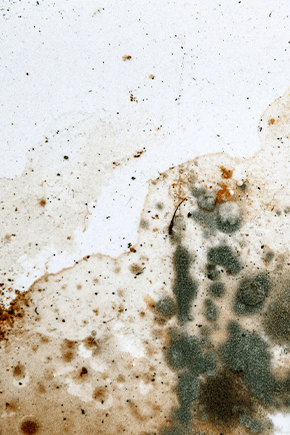

Dermatite Seborreica

A Dermatite Seborreica (DS) é uma doença inflamatória, normalmente confinada às áreas cutâneas de elevada produção sebácea, como o couro cabeludo e rosto. Os sintomas desenvolvem-se gradualmente e caracterizam-se por prurido ocasional, caspa e descamação gordurosa amarelada – casca oleosa.

Colonização fúngica por Malassezia

Um fungo naturalmente presente no couro cabeludo, mas que, nas pessoas com caspa oleosa, se encontra presente em excesso, e causando irritação, inflamação e descamação da pele.